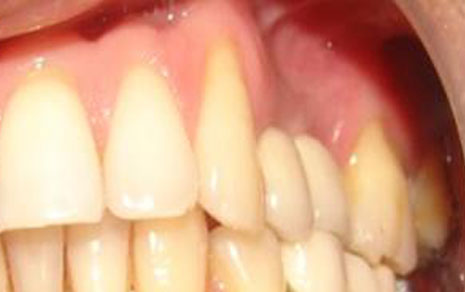

Multiple Implants

Restore several teeth while maintaining chewing function and jaw health.